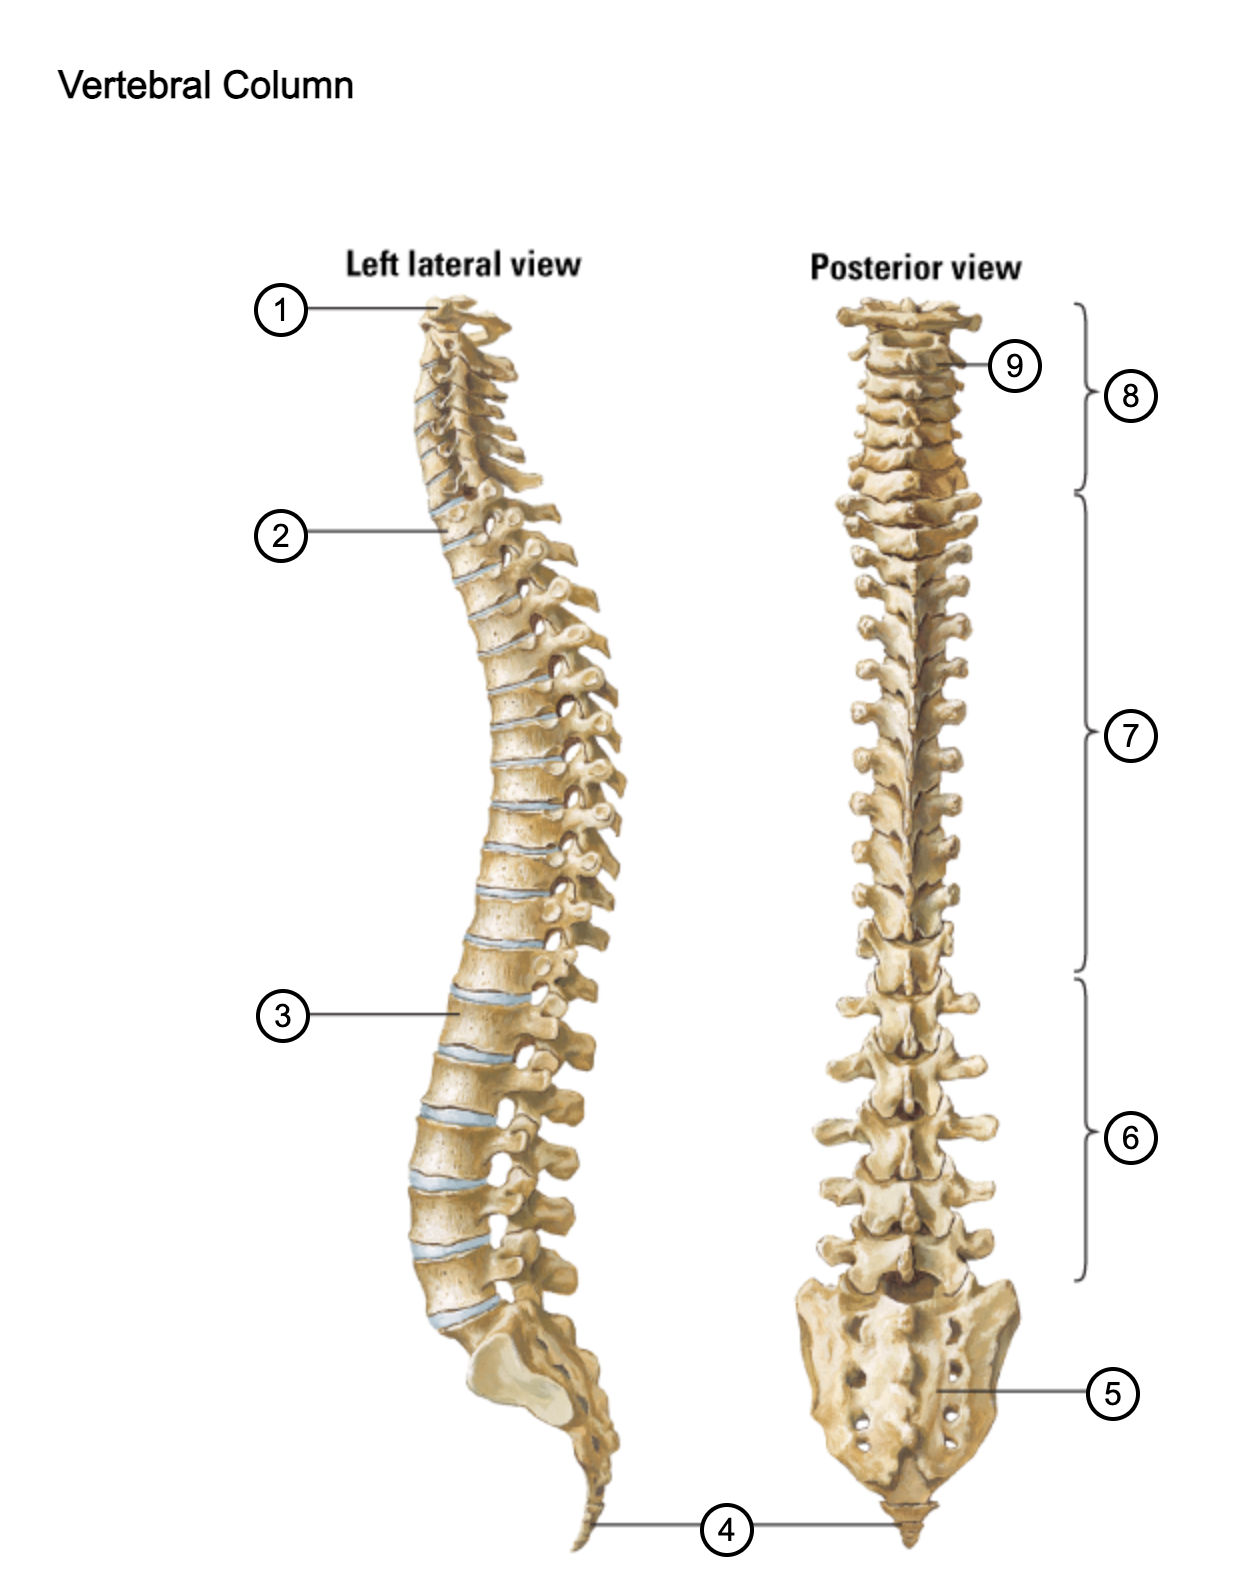

1

atlas (C1)

2

T1

3

L1

4

coccyx

5

sacrum (S1-5)

6

lumbar vertebrae

7

thoracic vertebrae

8

cervical vertebrae

9

axis (C2)